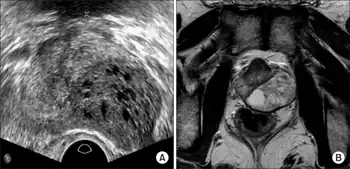

Prostatic stromal tumour of uncertain malignant potential (PSTUMP) is a rare tumour of the prostate gland stroma that may behave benign or like cancer.